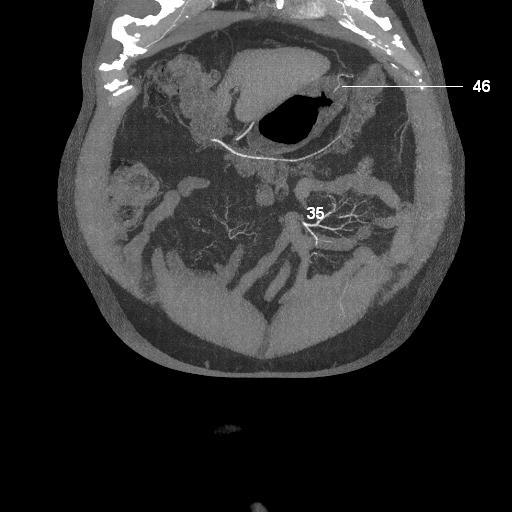

mesenteric arteriogram

35. jejunal arteries

46. left gastroepiploic artery